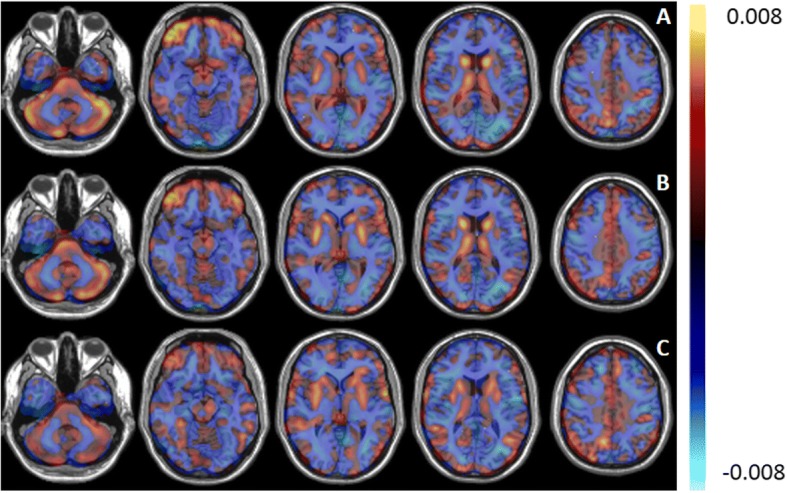

The average ROC curves obtained by SVM, PCA-SVM, and PCA-LR for direct classification between ALS and PP are given in Fig. 2. The corresponding AUC values are given in Table 1 together with the sensitivity and specificity. Furthermore, the Pearson correlation coefficient (r) between the individual pattern expression scores, as determined by the three classifier, is given in Table 3. For each classifier, the 3D discriminative pattern ATw (see Eq. 2), obtained by using all image data for training, is illustrated in Fig. 3. The values in each voxel are the weights of the contribution of the classifier. The positive values, marked in red, indicate regions of relative hypermetabolism in ALS patients compared to PP patients, whereas the negative values, indicated in blue, correspond to relative, regional hypometabolism in ALS patients compared to PP patients.

Second, we showed that different classifiers can be used to generate both disease-discriminative (Fig. 3) and disease-specific (Fig. 4) glucose metabolic brain patterns using 18F-FDG brain PET imaging. Since ALS patients match a positive and PP patients a negative pattern score, positive weights in the disease discriminative pattern constitute hypermetabolism in ALS patients compared to PP patients while negative pattern weights correspond to hypometabolic brain regions in ALS patients compared to PP patients. This same holds for the disease-specific ALS and PP pattern where an ALS or PP patient corresponds to a positive pattern score and thus positive pattern weights correspond to hypermetabolism in ALS and PP patients compared to healthy controls while negative weights represent hypometabolic brain regions in ALS and PP patients compared to healthy controls. Correlating the pairs of individual projection scores for a ALS- and PP-specific metabolic brain pattern determined by each of the three methods resulted in a RV coefficient of 0.93 on average (Table 3). Similarly, the voxelwise Pearson correlation coefficient for the disease-specific patterns demonstrated the strong correlation between ALS and PP patterns as determined by the three classifiers, with a lower correlation between patterns determined by SVM and PCA-LR (r value of 0.70 for ALS and 0.66 for PP respectively). The lower correlation between SVM and PCA-LR patterns could be explained by the fact that SVM and PCA handle noise and intersubject variability differently. Although, these patterns demonstrated visually the same main regions of hyper- and hypometabolism. Overall, the generated ALS- and PP-specific patterns were very similar to the ALS and PP patterns that have been discussed extensively in literature. Specifically, for ALS patients, relative hypometabolism in the frontal and parietal cortex and relative hypermetabolism in the anteromedial temporal cortex, in the absence of concomitant frontotemporal dementia, cerebellum, and brainstem have been observed [ref. 11]. In contrast, PP patients have relative hypometabolism in the striatum and according to the subtype, relative hypometabolism in the pons and frontal cortex (PSP), relative hypometabolism in the cerebellum (MSA), and a very asymmetric relative hypometabolic pattern in CBD [ref. 11, ref. 30–ref. 32]. As such, the generated PP pattern is a composition of different subtype patterns and therefore masks some subtype-specific characteristics such as the CBD-specific hypometabolic asymmetry. On the other hand, the highly accurate classification results implied that the generated patterns are to be considered as disease-specific for ALS and PP or discriminative between ALS and PP. Therefore, the glucose metabolic brain patterns reflect disease pathogenesis and hold information about diagnosis and prognosis. This way, this pattern not only supports differential diagnosis but can also have an added value for assisting visual reading.